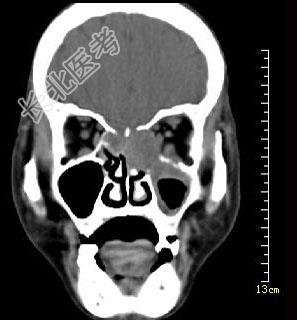

- 多项选择题男性50岁,涕中带血半年, 体检发现左侧颈部多个硬结,CT扫描如图所示, 请选择正确的描述和结论 ( )

A、左侧筛窦内见软组织块影,边缘不规则

B、软组织影累及对侧筛窦、左侧上颌窦

C、左侧眶内壁、上颌窦壁及颅底骨质破坏

D、考虑为左侧筛窦黏液性囊肿

E、考虑为左侧筛窦癌